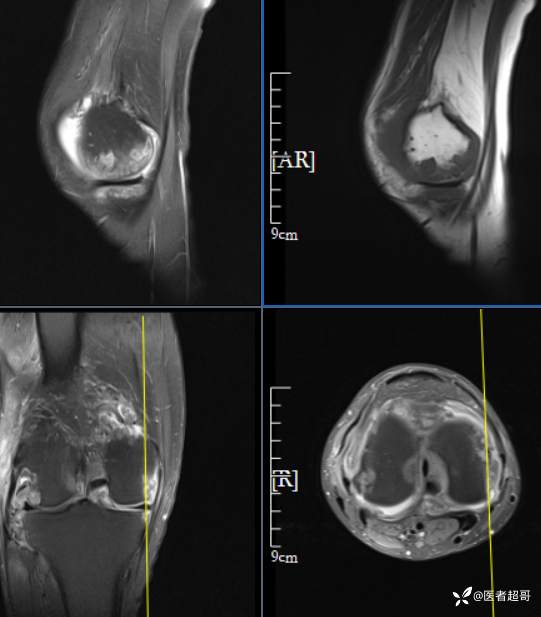

华夏览雄 等 2 位达人已点赞男性,55岁,右膝关节疼痛伴活动困难2年余

两年前外院行右膝包块切除术,术后病理为“肉芽肿”,具体不详,患者术后经常右膝关节积液,右膝活动困难,右膝疼痛明显

实验室检查:白细胞计数:9.0×10^9/L;葡萄糖(空腹):6.93mmol/L↑